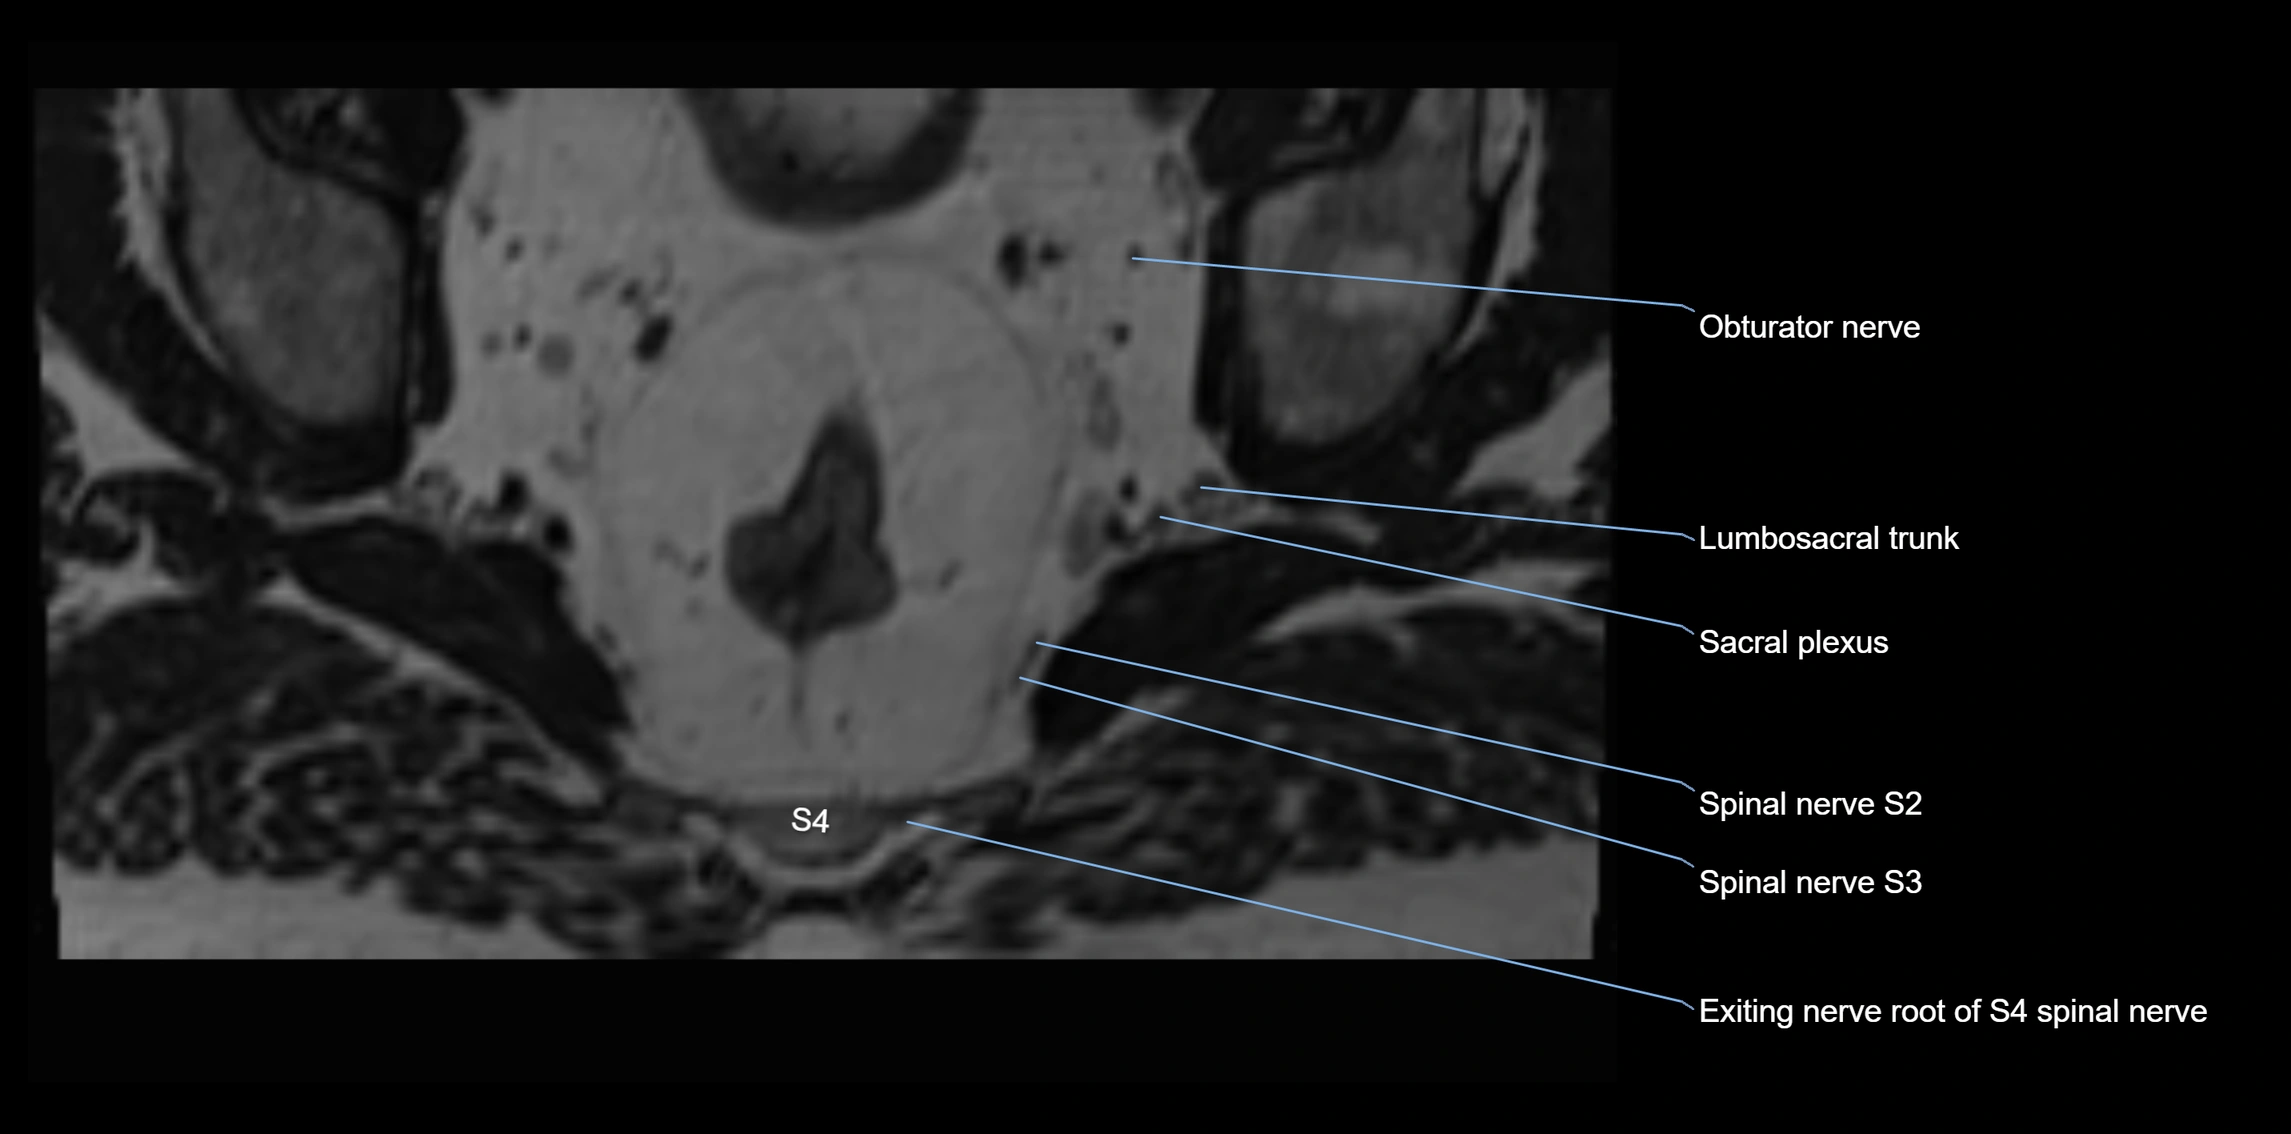

MRI Appearance

T1-weighted images:

• Nerve appears as a very thin low-to-intermediate signal intensity structure

• Surrounded by bright fat, aiding visualization

T2-weighted images:

• Nerve shows intermediate to mildly hyperintense signal compared to muscle

• Pathological involvement appears brighter

STIR (Short Tau Inversion Recovery):

• Normal nerve appears dark

• Inflamed or entrapped nerve appears bright hyperintense

T1 Fat-Sat Post-Contrast:

• Normal nerve enhances minimally

• Pathologic nerve (neuritis, entrapment, tumor infiltration) shows focal or diffuse enhancement

3D T2 SPACE / CISS:

• Nerve appears intermediate to mildly hyperintense compared to muscle

• Surrounded by bright fat or CSF, improving visualization

• Best sequence for mapping small pelvic nerves such as the anococcygeal